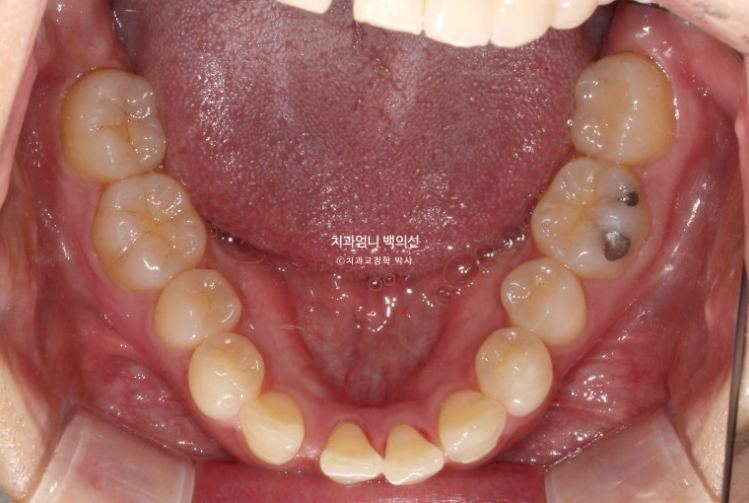

아래 앞니 4개 중 2개가 없습니다.

태어날때부터 없는 경우를 선천적 결손이라고 합니다.

단 이경우 아래 송곳니는 결손된 앞니 자리로 끌어와 앞니로 대체하고 아래 작은어금니를 송곳니 자리로 끌어와 송곳니로 대체합니다.

이렇게 하면 어금니도 정확한 1급 교합관계 달성이 가능합니다.

아래는 송곳니를 앞니자리로 끌어오는 중입니다.

파란화살표는 사실 앞니가 아니라 송곳니 입니다.

어금니 교합관계는 정확히 1급입니다. 송곳니 자리에 있는 파란 화살표는 사실 송곳니가 아니라 첫번째 작은어금니입니다.